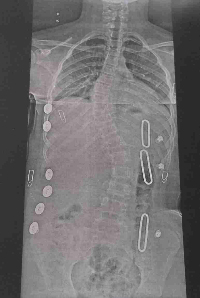

Porém tem uma condição genética de *Escoliose idiopática* que ainda não tem causa definida pela medicina. Ela Nasceu com a coluna vertebral normal, porém com o passar dos anos ela começou a entortar. Há uma medição da curvatura que aumentou em 30° em 1 ano, uma progressão muito agressiva, precisando assim de um colete em 3D e fisioterapia.

Esse colete 3D é feito sob medida, e terá que ser trocado de *8 meses a 1 ano* conforme o crescimento até que ela faça 17 anos de idade e conclua a maturidade esquelética da coluna. Hoje estamos numa corrida contra o tempo para comprar o colete 3D e uma cama com colchão mais confortável, pois ela terá que usar o colete 23 hrs por dia. Além de precisar de transporte e alimentação pois ele é feito no Rio de Janeiro capital.